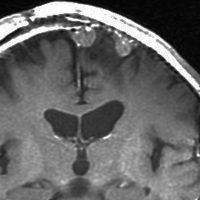

左は,造影剤を使ったガドリニウム増強MRIです。腫瘍が白く丸く見えます。右はフレア画像で,腫瘍の周囲の脳浮腫(脳のはれ)です。左前頭葉が,かなり強くはれています。この腫瘍は小さいのですが,脳のはれが強すぎるので手術摘出したほうがいいです。浮腫が悪化すると,てんかん発作や認知機能低下がでる可能性があります。

MRIでの髄膜腫の見え方は撮影の仕方によっていろいろです。左からT1強調画像,T2強調画像,フレア画像といいます。腫瘍の横に小さく白い領域がありますが,これは脳の腫れた部分で脳浮腫といいます。髄膜腫があると周囲に脳浮腫が生じることがあります。

最も見やすいのが,ガドリニウム造影剤を注射して撮影するものです。一般的に髄膜腫は造影剤で白く映し出されます。この腫瘍は左脳側にあります。MRIの軸面という輪切りの写真では左右が逆になりますから注意してください。脳を下から見た図になっています。MRIはいろいろな方向から腫瘍を見ることができますが,右は冠状断という正面から見た図です。よく見ると腫瘍の上と下のはじっこに線状に糸を引いたように造影される部分があります。これをテールサイン(しっぽのサイン)といいます。腫瘍が硬膜に沿って延びている可能性があることを示しています。